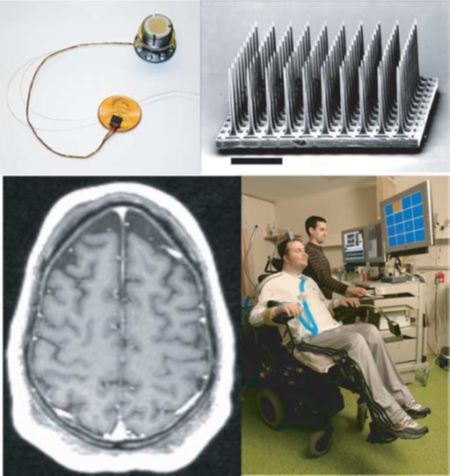

2004年,美国Cyberkinetics公司将电极芯片植入到人脑中,志愿者能够利用脑电来收发电子邮件。现在,瑞士科学家已经推出了经训练后可用思想控制的轮椅模型。人脑中渺不可见的神经元与物质世界相连接,打开了一条通往未来的道路。在人工智能领域,脑机接口一向被视作代表未来的技术。大脑中有着200亿左右个神经元,掌握这些黏糊糊的晶体管,我们就能让思想产生无限飞跃。“我们所想象的一切,都将变为现